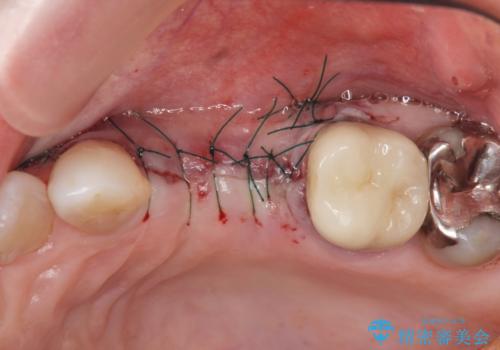

歯の穿孔(内部穴が開いている状態)破折等、歯を保存することができない問題が小臼歯には認められたので抜去を行います。

抜去後の補綴治療は長いブリッジではなくインプラント治療を希望されましたが、穿孔・破折による周囲の骨吸収をリカバリーすべく骨の造成を伴うインプラント治療を計画します。

インプラント治療を行うにはインプラント周囲に十分な骨の幅・高さが必要です。

今回はが原因で失われてしまった骨の幅を回復することで長期的な予後を見込めるインプラント治療を行うことができました。